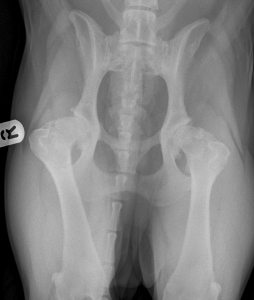

Η πάθηση χαρακτηρίζεται από αρθρική χαλαρότητα (η κεφαλή του μηριαίου δεν εφαρμόζει αρμονικά στην κοτύλη), που έχει ως συνέπεια την ανώμαλη τριβή των αρθρικών επιφανειών και την ανάπτυξη οστεοαρθρίτιδας διαφόρου βαρύτητας (Εικόνα 1).